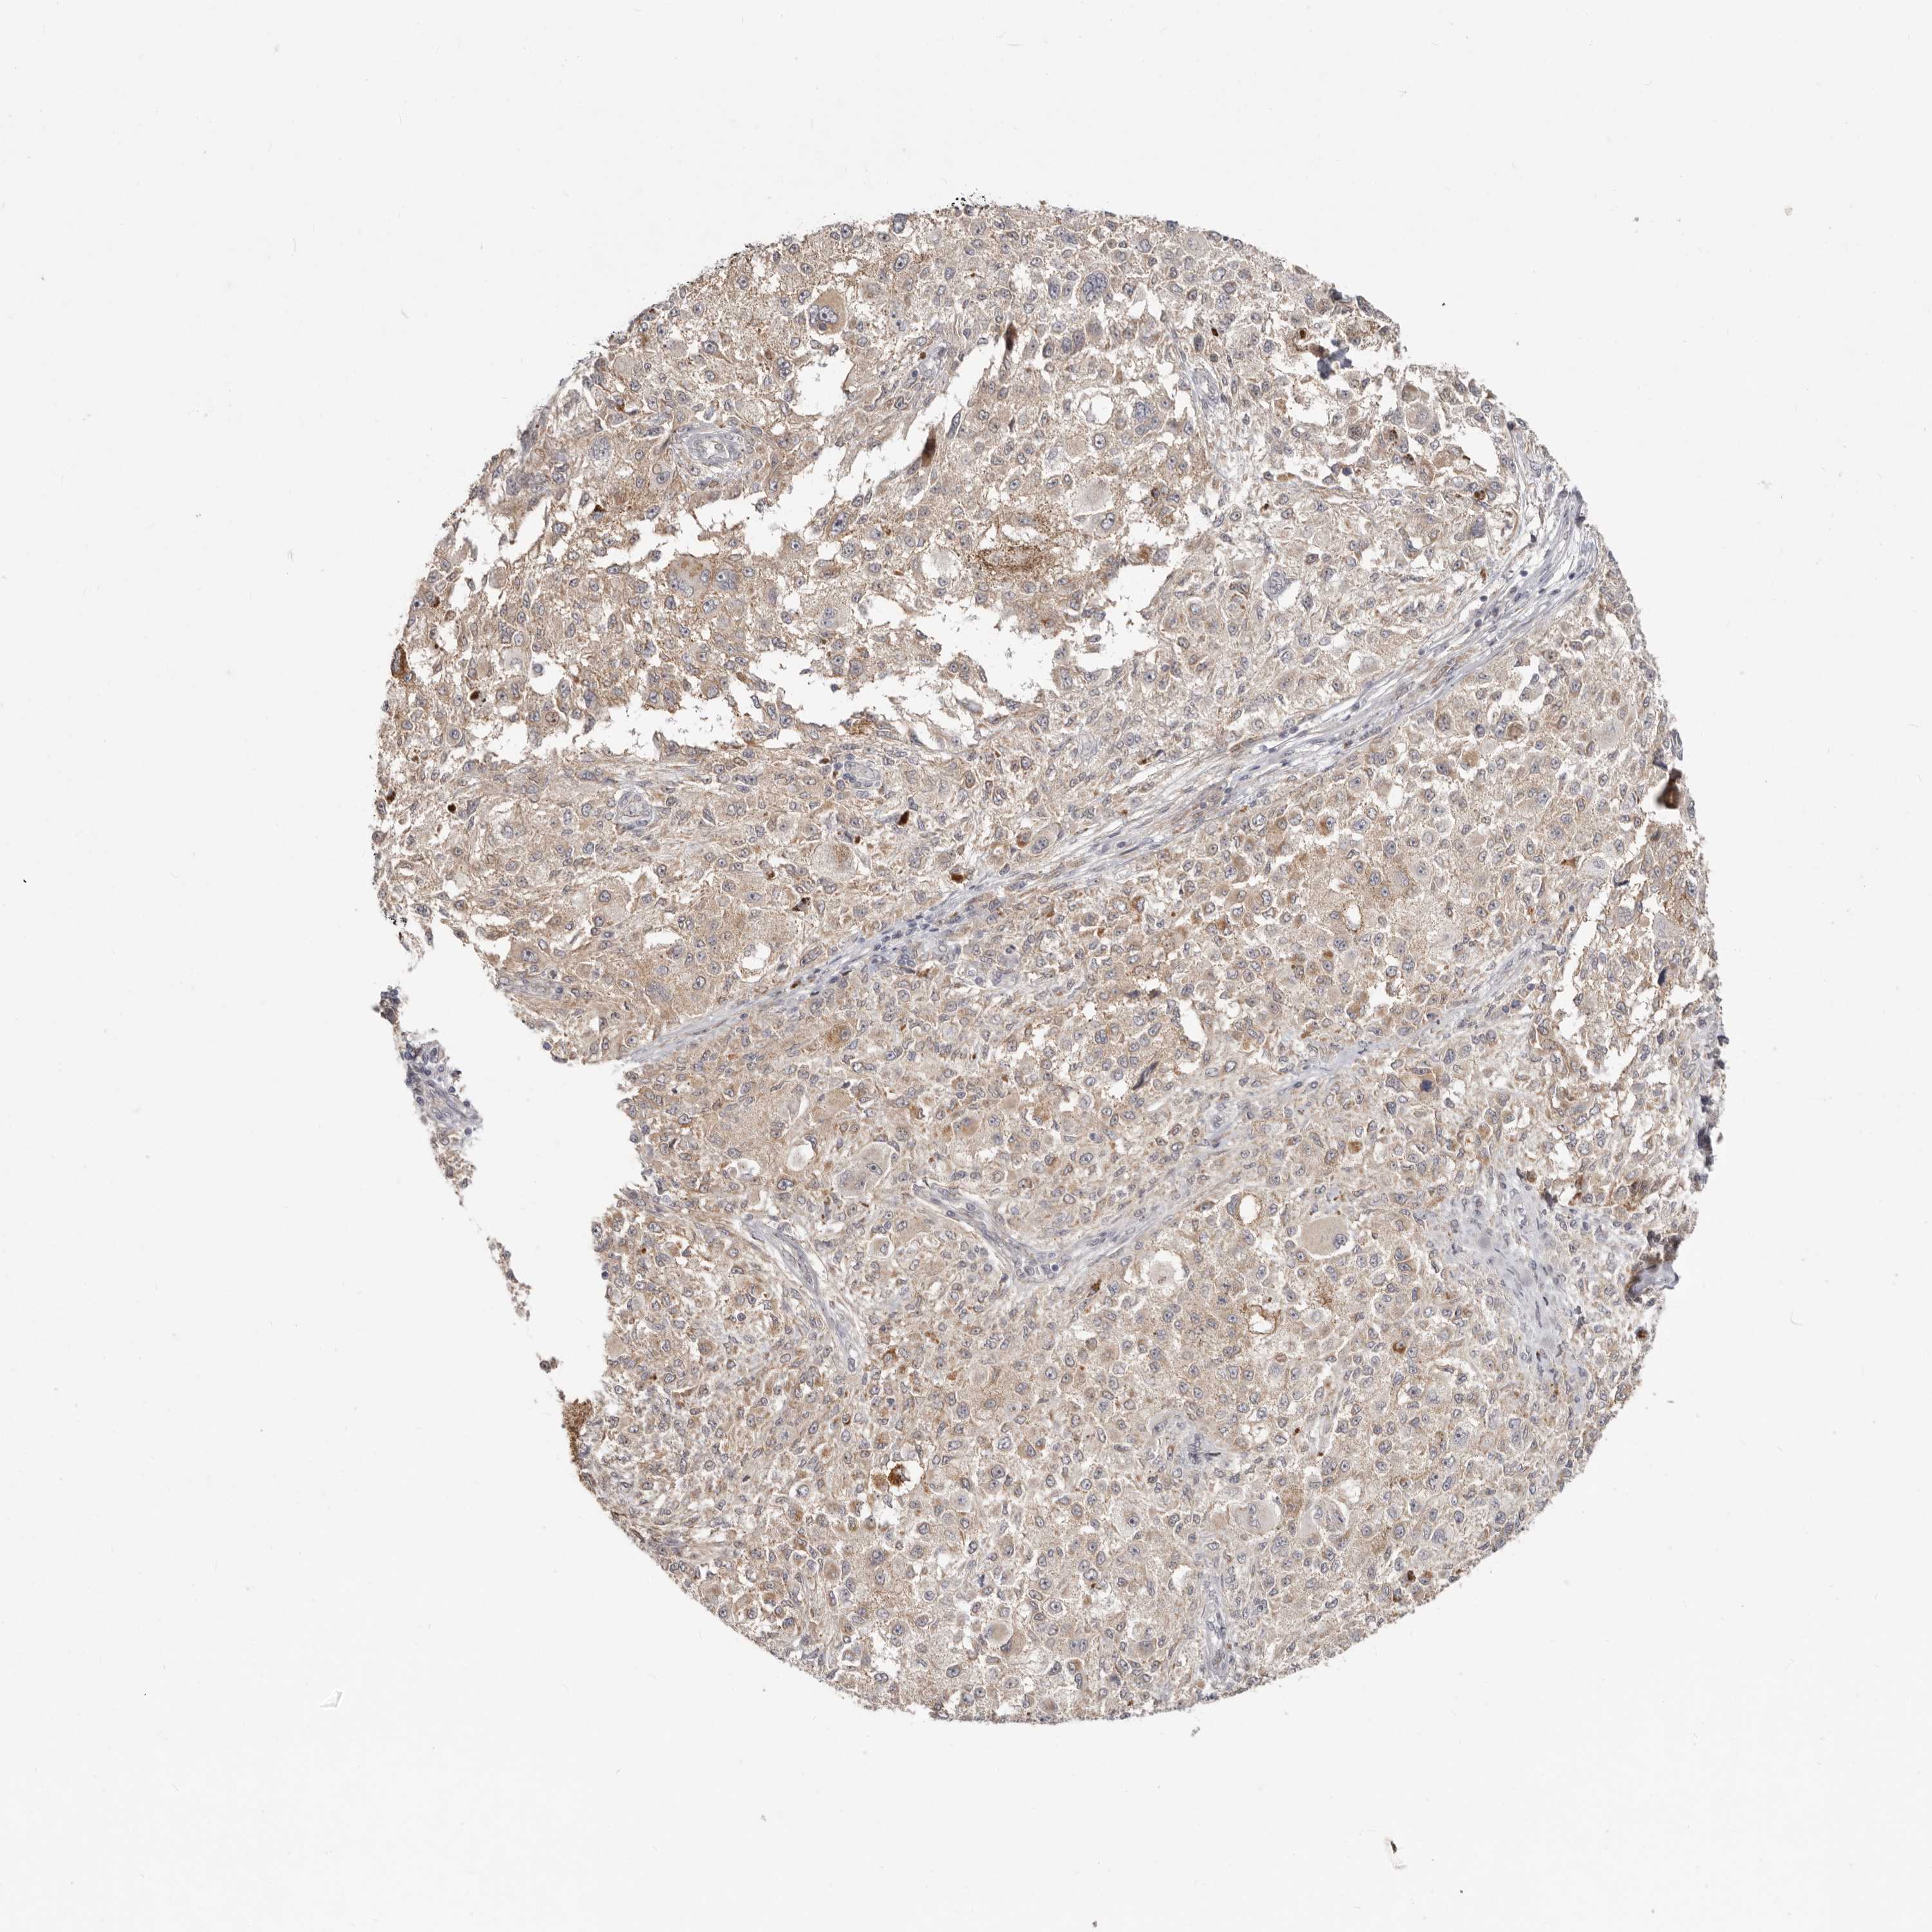

MELANOMA - Protein expressioni

A mouse-over function shows sample information and annotation data. Click on an image to view it in a full screen mode. Samples can be filtered based on level of antibody staining by selecting one or several of the following categories: high, medium, low and not detected. The assay and annotation is described here.

Note that samples used for immunohistochemistry by the Human Protein Atlas do not correspond to samples in the TCGA dataset.

Antibody stainingi

Antibody staining in the annotated cell types in the current human tissue is reported as not detected, low, medium, or high, based on conventional immunohistochemistry profiling in selected tissues. This score is based on the combination of the staining intensity and fraction of stained cells.

Each image is clickable and will lead to virtual microscopy that enables deeper exploration of all samples and also displays staining intensity scores, fraction scores and subcellular localization as well as patient and tissue information for each sample.

Antibody HPA029012

Staining

High

Medium

Low

Not detected

Intensity

Strong

Moderate

Weak

Negative

Quantity

>75%

75%-25%

<25%

None

Location

Nuclear

Cytoplasmic/membranous

Cytoplasmic/membranous,nuclear

Malignant melanoma, NOS

Malignant melanoma, Metastatic site